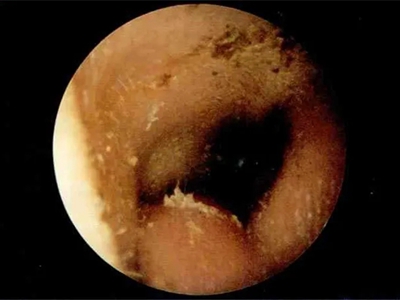

外耳道

结痂

外耳道炎外耳道结黄痂图

外耳道炎在检查时显示有很多黄色分泌物,附着在外耳道黏膜壁上,脓痂上还有白色豆腐渣状的鳞屑堆积,患者自觉耳痛、瘙痒、耳道潮湿。